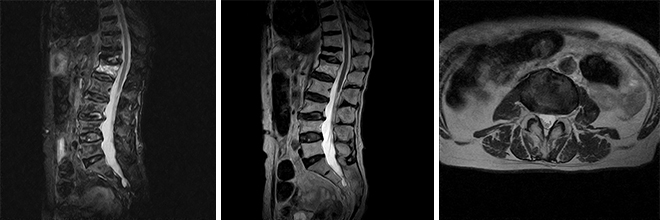

腰椎MRI

整形外科領域のあらゆる疾患・傷害の診断に役立ちます

- 頚椎、腰椎、椎間板の断層撮影

- 神経疾患、脊髄疾患、神経痛の原因診断